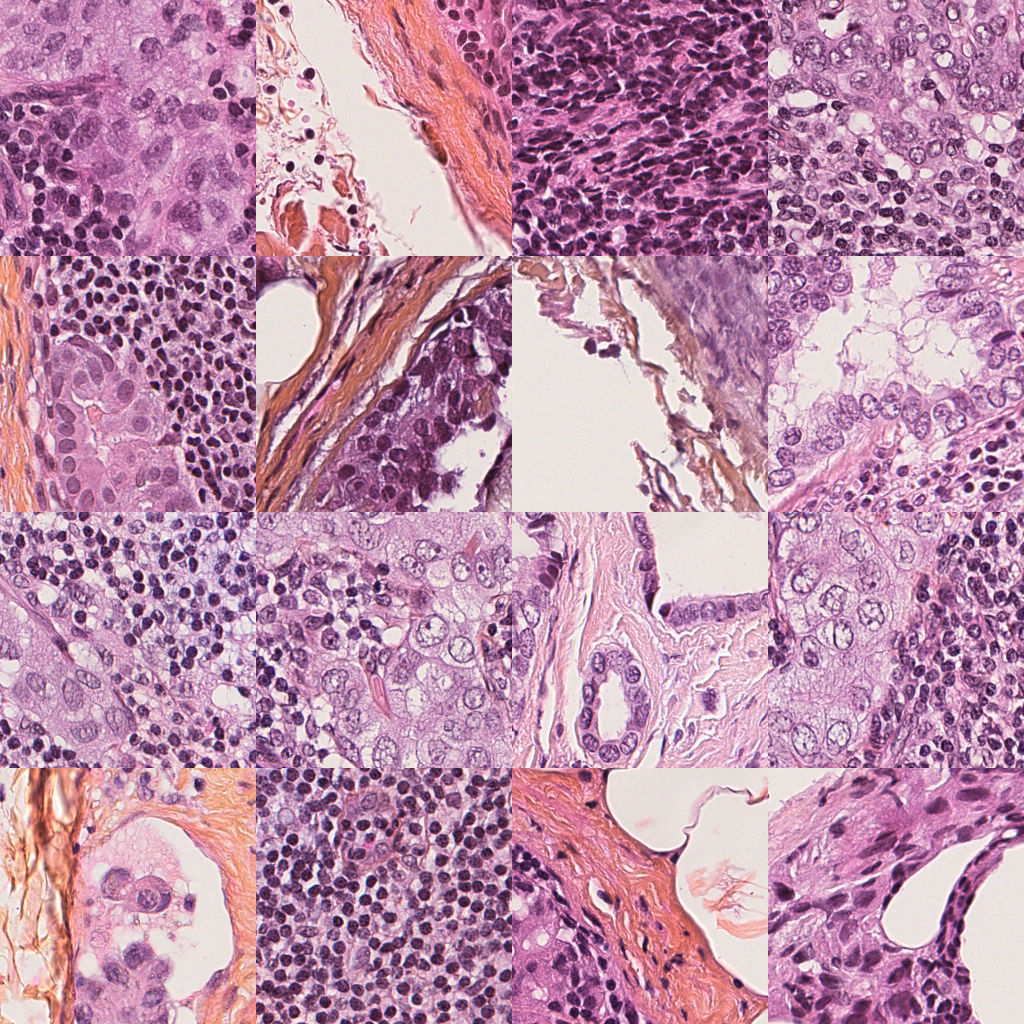

Our primary means of evaluating model performance is with the expert H&E annotations. This provides a good first approximation to the locations of the cancer cells, and where the DAB should appear once the stain transfer has been performed, even though annotation contours often bisect healthy tissue regions or otherwise contain normal cells. For each of our trained generators, we first produce the IHC stain for each of a set of 500500500 held-out test H&E tiles. We visualise samples of these in Figure 3 for both the proposed model and the baseline CycleGAN 8×8888\times 8, alongside the annotation. One may observe the accuracy of our proposed model in localising the DAB stain. Although we observe a weak correlation between positive tiles and the presence of DAB, the baseline CycleGAN systematically misplaces the DAB stain. This localisation problem was observed across all competing models. We hypothesise our proposed model profits from the object-level supervision, with our proposed RoI discriminator performing discrimination directly centered on cells.

Refer to caption

(a) Input images

(b) Annotation

(c) CycleGAN

(d) Region-guided CycleGAN

Figure 3: Sample H&E tiles from the GR dataset (a); with corresponding ground truth annotation masks (b); baseline CycleGAN stain transfer (c); and proposed region-guided stain transfer (d).